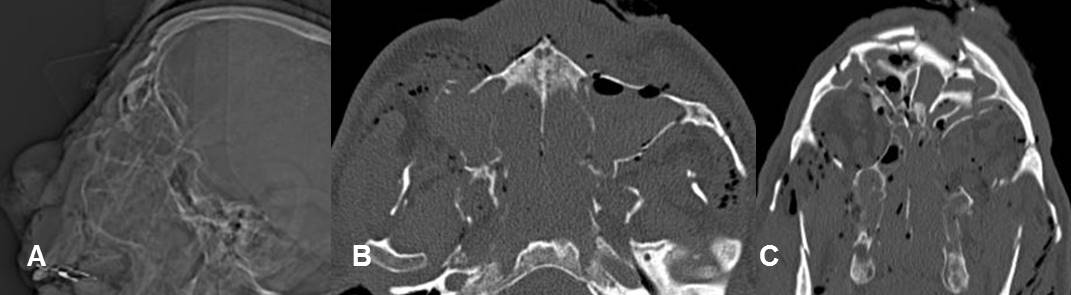

Fig 227. Lefort III.

A: Rx lateral, B: TAC axial y C: TAC reconstrucción coronal. Severo estallido facial con fracturas deprimidas de la parte anterior de la cara y Lefort III bilateral.